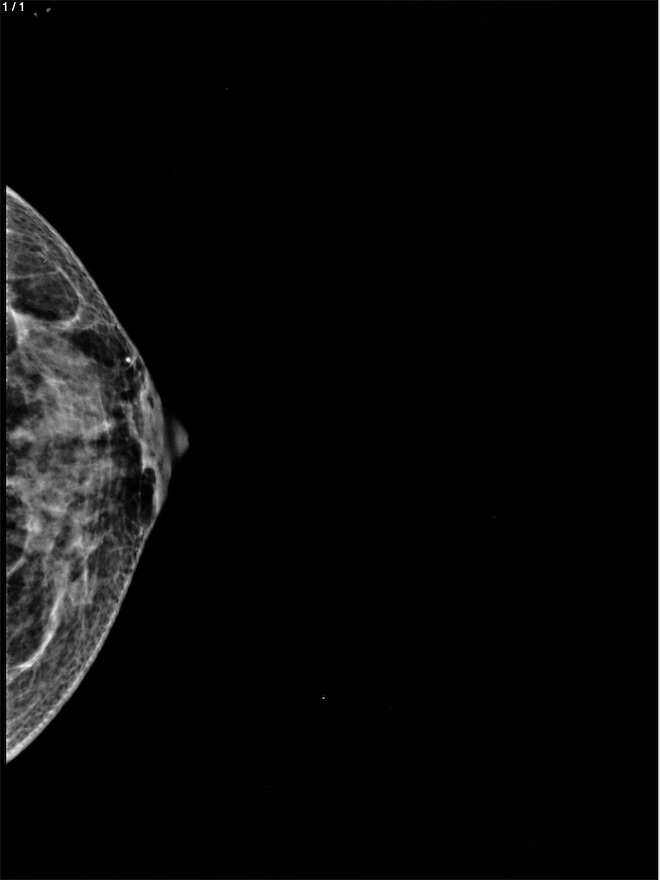

Gisela Castillo Hernandez - Unnamed